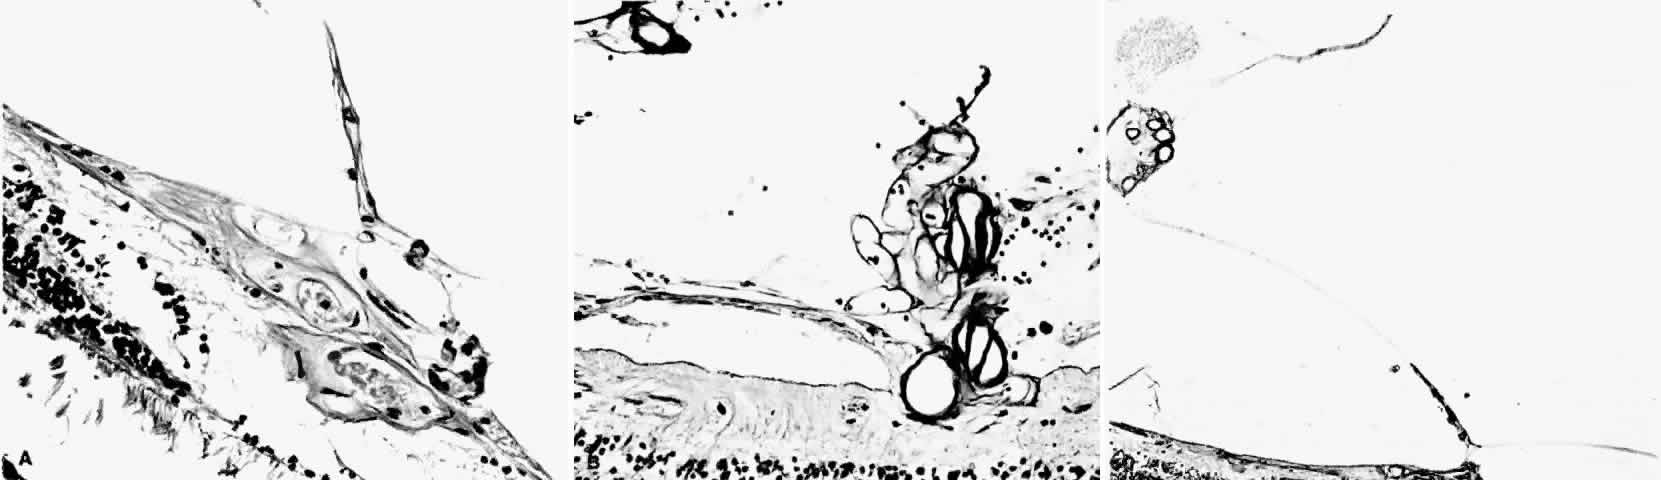

PSR is associated with the severe vision-threatening sequelae of sickle cell disease: vitreous hemorrhage (stage IV) and retinal detachment (stage V). These stages are believed to result from transudation of blood components into the vitreous through the incompetent neovascular tissue (Fig. 28). Vitreous fluorophotometry has quantified the leakage from the peripheral neovascularization.134 This leads to premature syneresis and collapse of the vitreous, inducing tractional forces on the retina that lead to vitreous hemorrhage, retinal tears, and tractional and rhegmatogenous retinal detachment. In rare cases, an exudative detachment may occur.

Fig. 28. A. Cross-section of retina shows vitreous adhesions to flat neovascular tissue (stage III proliferative sickle cell retinopathy [PSR]).Fig. 28 (continued).B. Cross-section of retina reveals large clump of neovascular tissue (stage III PSR) protruding from surface of retina into vitreous. C. Cross-section of retina and vitreous. Note large cluster of intravitreous neovascular tissue adherent to vitreous traction bands. (Romayananda N, Goldberg MF, Green WR: Histopathology of sickle cell retinopathy. Trans Am Acad Ophthalmol Otolaryngol 77:652, 1973.)